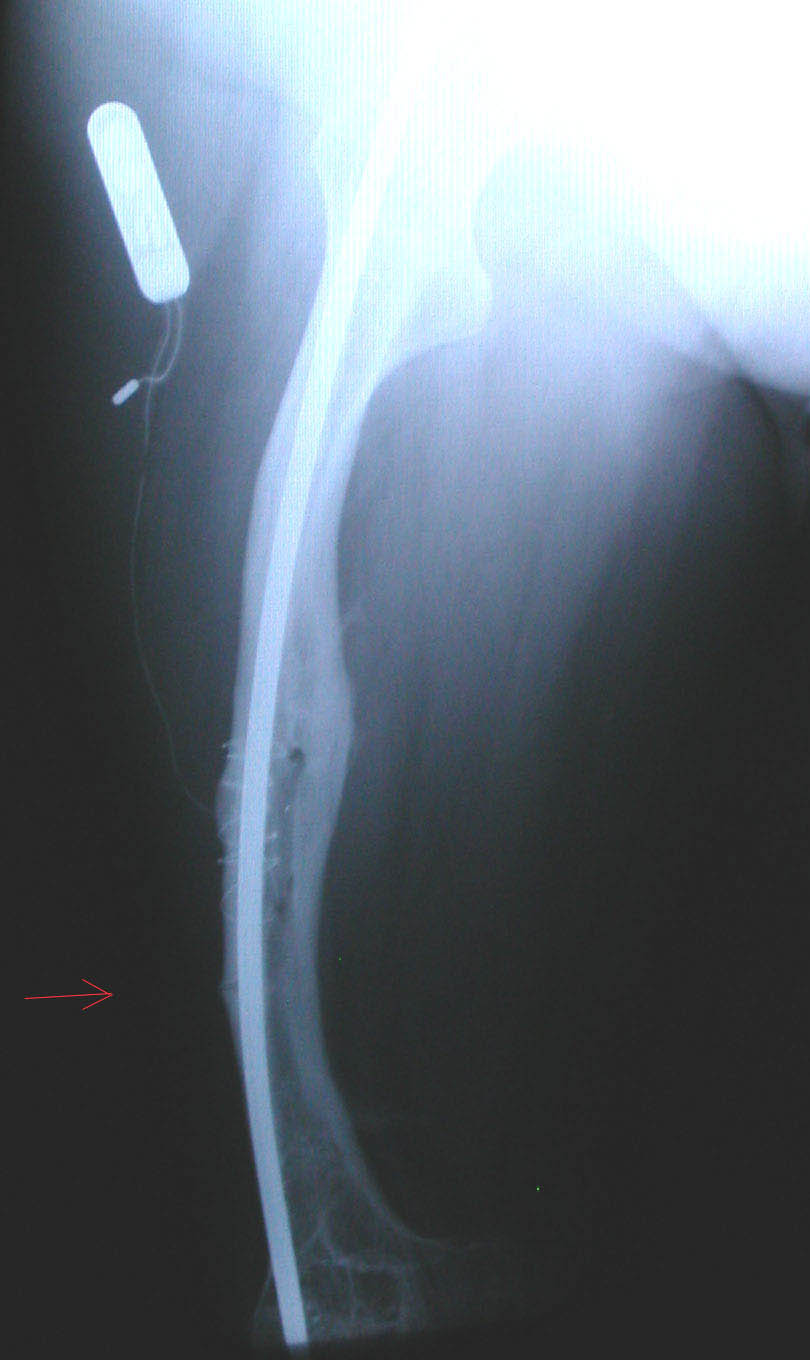

Adulto tipo IV. 42 años. Fisura en fémur derecho.

El paciente lleva un clavo intramedular y un antiguo electroestimulador de callo óseo de una fractura anterior.